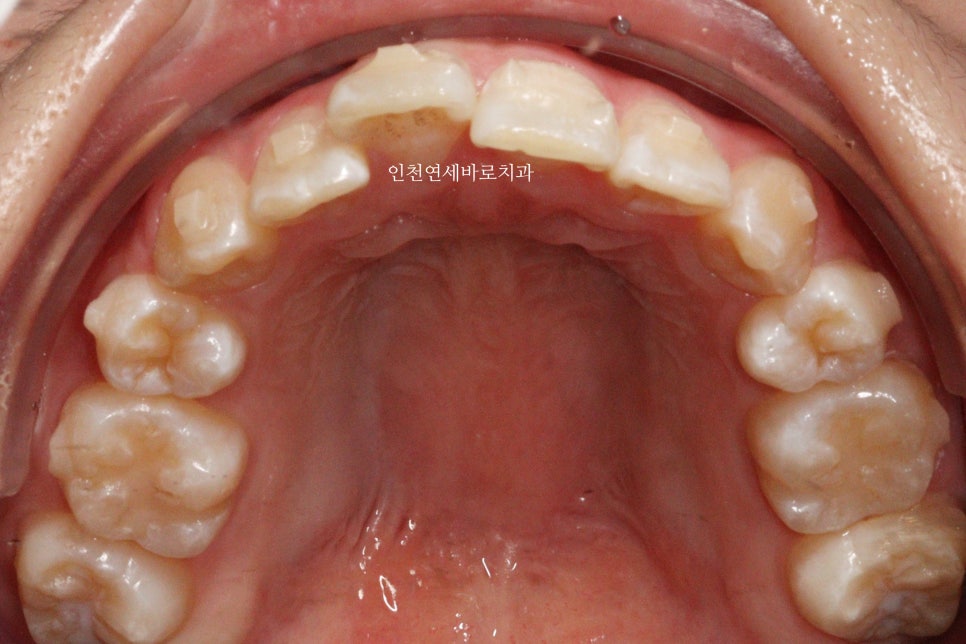

변화모습입니다.

약 3개월의 변화모습입니다.